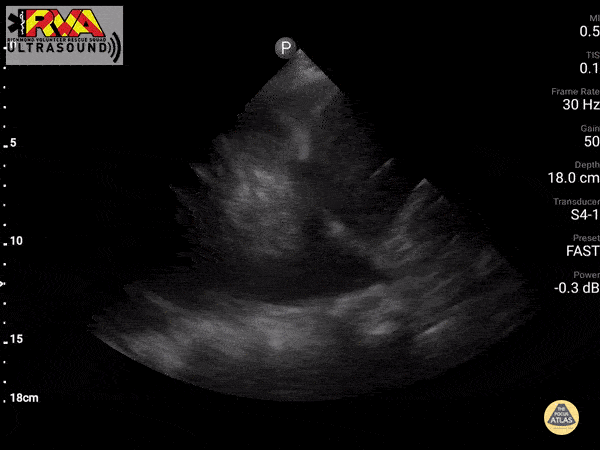

This 80 year old male with a history of Alzheimer's with recent accelerated decline experienced a fall from bed. Though the only visible trauma involved a laceration above the right eye, globally diminished breath sounds were noted, and a prehospital eFAST exam was performed. Pictured is a large, right-sided pleural effusion, with visible spine sign observed during the exam. No other abnormalities were observed. With the absence of significant chest trauma, the effusion was assumed to be non-traumatic in origin. Due to the patient's recent rapid decline, family elected to manage conservatively, and the patient was admitted to palliative care. - Tom Hudson, NRP, CCP-C (Richmond Volunteer Rescue Squad)